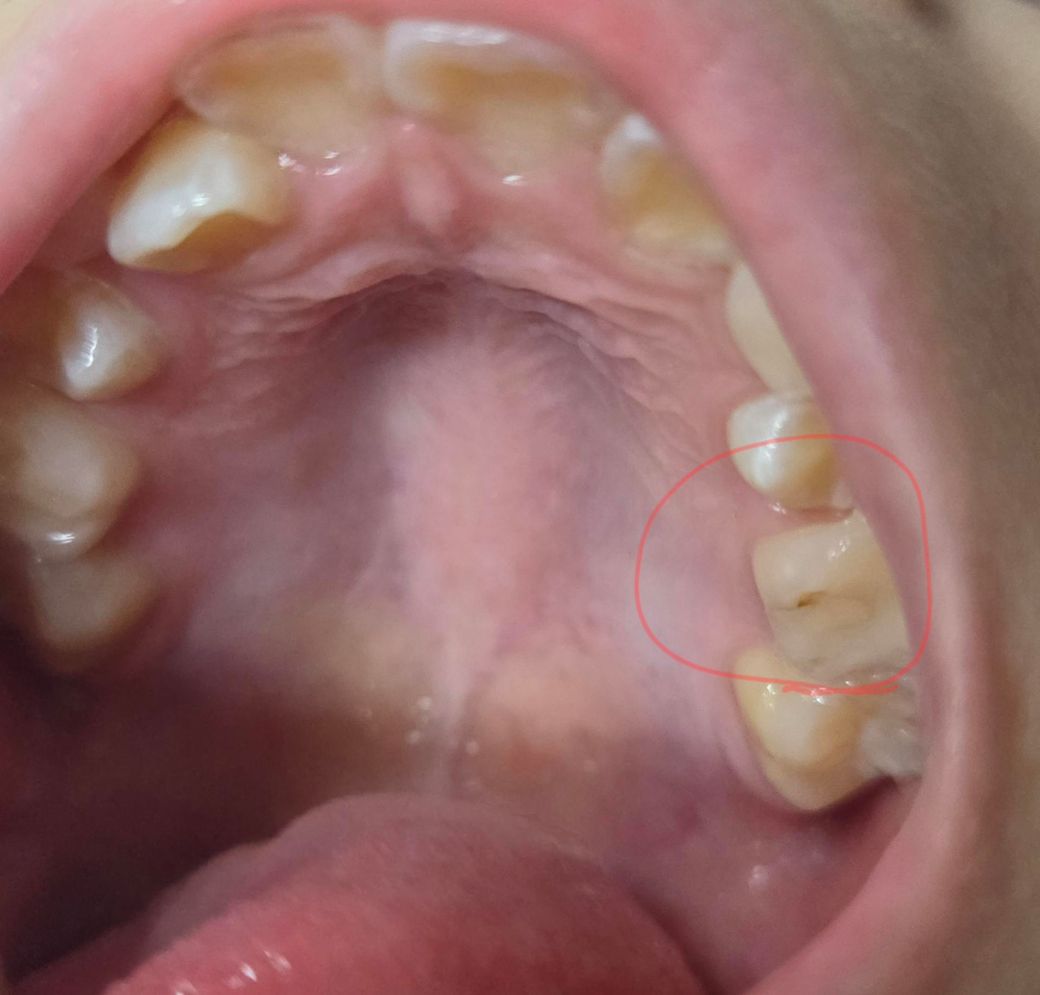

10살 딸 치아인데 이거 충치인가요?

10살 딸 양치전에 치실하다가 발견했는데 이거 충치인가요? 충치라면 가장 좋은 치료법은 뭔가요?? 레진으로 때우나요?답변부탁드려요

사진상으로는 예전에 떼웠던 곳 밑으로 충치가 진행되고 있어 보이며 레진치료 받으시면 됩니다.

충치 맞습니다. 어느 정도 진행된 것으로 보입니다. 신경치료 할 정도는 아닌 것으로 보이며 레진이나 다른 재료로 때우면 될 것으로 보입니다.

예전에 레진으로치료를 한거 같습니다. 아마 레진이 깨지면서 착색 및 2차 충치가 생긴거 같습니다.

사진으로 봐서는 충치보다는 변색같기도 합니다. 만약 치료가 필요하다면 유치이고 곧 순서대로 빠질 치아라 레진말고 보험되는 gi재료로 하는 것도 나쁘지 않을 것 같습니다.